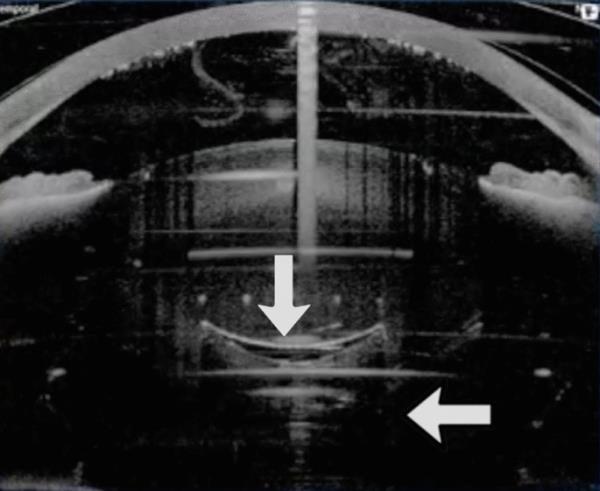

图1

figure 1

囊膜切开后眼倾斜,此时碎片量已经设定。这导致后囊部分被飞秒激光切割